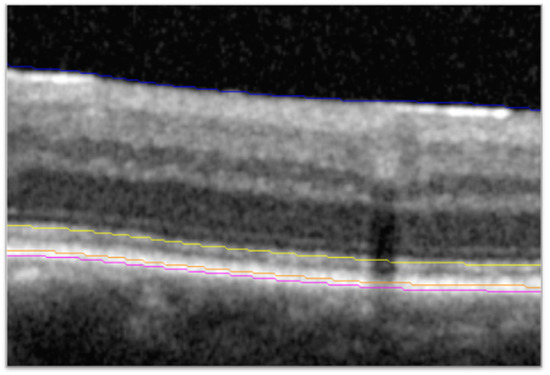

SD-OCT scans (Cirrus, Zeiss [Oberkochen, Germany]; or Spectralis, Heidelberg Engineering [Heidelberg, Germany]) from the brolucizumab 6 mg and aflibercept 2 mg treatment groups collected during the HAWK study were sent to the Cleveland Clinic (Cleveland, OH, USA) for post hoc analysis. The HAWK trial included n = 360 eyes in the brolucizumab 6 mg arm and n = 360 eyes in the aflibercept 2 mg arm, of which 30 eyes and 38 eyes, respectively, were excluded for various reasons including image quality, availability, or compatibility. Scan acquisition for SD-OCT was the 6 × 6 mm macular cube with 128 B-scans for Cirrus and the 20° by 20° macular cube with 97 B-scans for Spectralis. Segmentation and identification of features on the SD-OCT scans utilized a previously described and validated process consisting of automated segmentation with a machine learning-based segmentation and feature extraction platform, followed by reviews and corrections or validation of segmentation by certified readers [9]. Previous validation showed inter-reader, intraclass correlation coefficients for metrics assessed with this process, including thickness from the EZ to the retinal pigment epithelium (EZ-RPE thickness), to be >0.9 in nAMD [10]. Each macular scan was automatically segmented to identify fluid boundaries and retinal layers of interest (i.e., EZ; Figure 1). A higher-order classifier then determined whether retinal fluid was SRF or IRF. Two masked certified readers evaluated segmentation accuracy, manually correcting any segmentation errors, as needed. The expert certified readers received the same SD-OCT analysis training, and the same reader reviewed and corrected any errors for a given participant across all time points, thus minimizing inter-time point and inter-reader variability. The reading environment was standardized with respect to location, computer configuration, monitor settings, and in-room lighting. The second senior image analyst then reviewed all scans to confirm accuracy and consistency of segmentation. Metrics exported for analysis at each time point included IRF and SRF volume across the macular cube and EZ-RPE central subfield thickness (CST). The central subfield was defined as the 1 mm diameter area centered on the fovea. EZ-RPE CST was calculated as the mean thickness of retinal tissue from the EZ to the RPE in the central subfield.

Figure 1. Identification of the EZ and RPE bands. SD-OCT B-scan showing line segmentation of the ILM (blue), EZ (yellow), RPE (orange), and Bruch’s membrane (magenta). EZ, ellipsoid zone; ILM, internal limiting membrane; OCT, optical coherence tomography; RPE, retinal pigment epithelium.